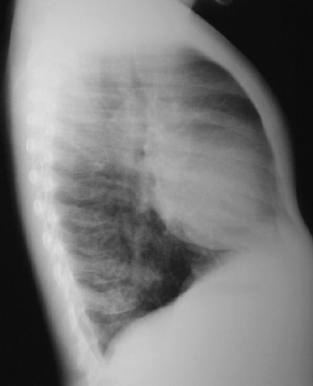

Radiología del tórax Pos operatoria

Rx.Tórax Pa. y L izq. 48 horas pos operatorio: Radiografía rotada por posición antalgica, el drenaje del tórax, la cisura transversa y lobulos superior e inferior expandidos, disminución del volumen pulmonar derecho, mediastino lateralizado a la derecha.